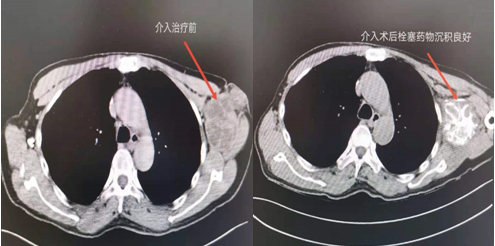

介入術(shù)前及術(shù)后CT對比圖

近日,吉林國文醫(yī)院淋巴瘤科與介入一科相互合作,成功為一例皮膚惡性黑色素瘤患者,實施了實體腫瘤動脈灌注化療栓塞術(shù),患者李某某10個月前曾確診為皮膚惡性黑色素瘤,腫瘤分布在左側(cè)腋下,患者既往曾多次行靜脈化療及免疫治療,但腫瘤病情仍然繼續(xù)進展,患者目前左側(cè)腋下腫瘤病灶增長較快,伴有局部脹痛感,淋巴瘤科左淑波主任綜合分析患者病情后,邀請介入一科韓長清主任進行共同商討治療方案,評估是否可行介入手術(shù)治療,經(jīng)兩位主任共同商討后決定,可給予患者行腫瘤供血動脈化療栓塞術(shù)介入治療。介入術(shù)中非常順利,成功尋找到腫瘤供血動脈并給予治療,術(shù)后患者恢復良好,疼痛癥狀有所改善。